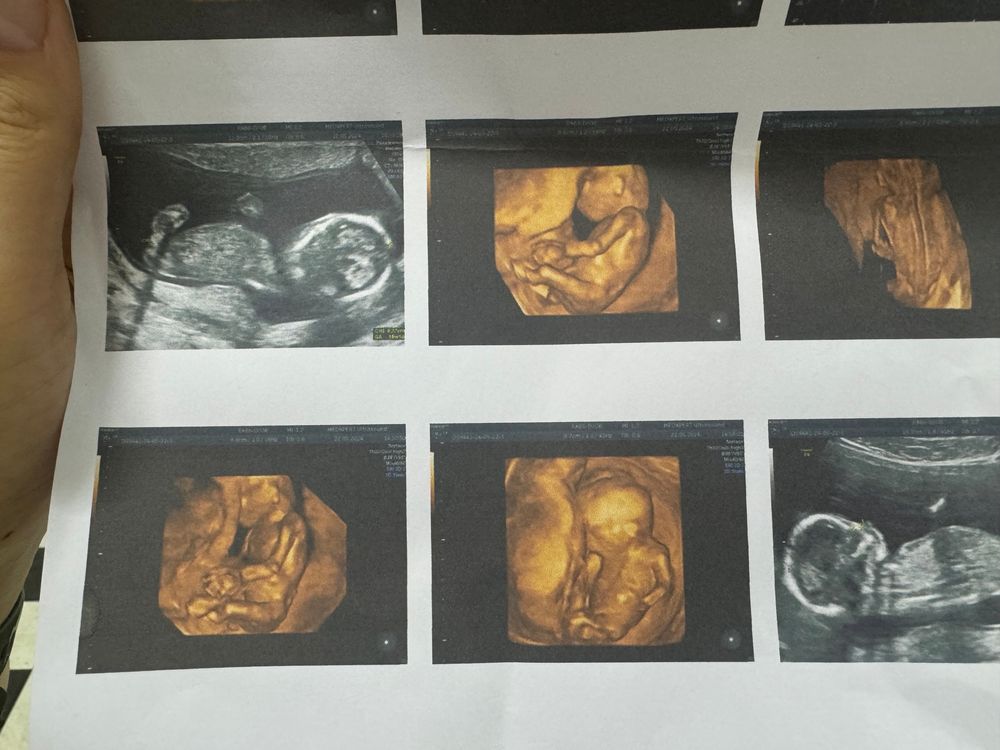

Asel в Благополучная беременность год УЗИ в 14 недель УЗИ, КТГ, доплер УЗИ в 14 недель пожалуйста кто разбирается это девочка да Посмотрите еще 20 записей на эту тему Лучший ответ Надежда я мальчика вижу 10.07.2024 Ответить Отменить Ответить Гроза Райисполкома Это мальчик) 10.07.2024 Ответить Serenity Вроде очень на мальчика похоже 10.07.2024 Ответить Вероника Какая милота 10.07.2024 Ответить Asel 10.07.2024 Ответить Asel Asel, вот еще )) 10.07.2024 Ответить Вероника А на УЗИ не сказали? 10.07.2024 Ответить Asel Вероника, нет , воообще отказался сказал только во втором скрининге точно скажу сказал 10.07.2024 Ответить Без одного дня 6 недель, узи Шейка и воды в 29 недель Чаты Беременных Выберите чат: Январята-2026 Февралята-2026 Мартята-2026 Апрелята-2026 Майчата-2026 Июнята-2026 Июлята-2026 Августята-2026